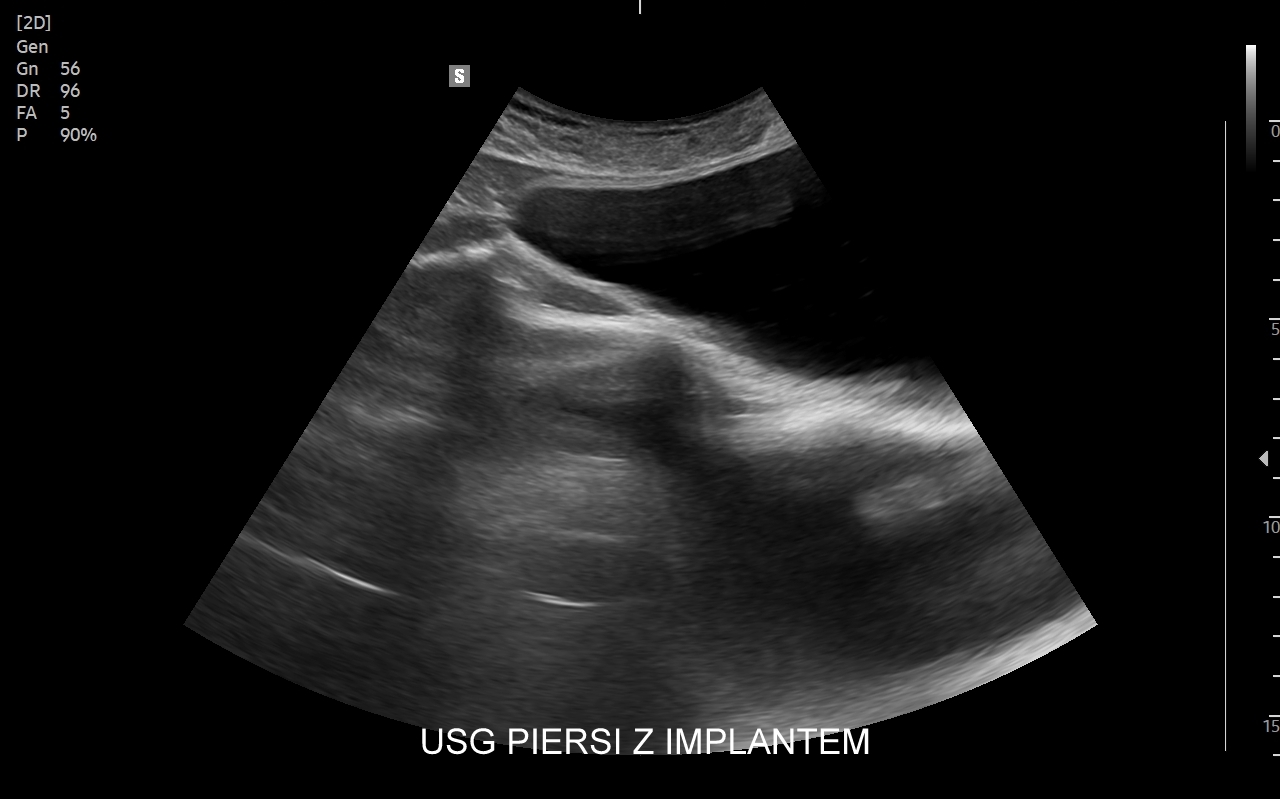

USG piersi z implantami

Badanie USG piersi z implantami jest szczególną procedurą diagnostyczną. Przeprowadza się ze wskazań wcześniej opisanych, jak w przypadku piersi bez implantów, ale także w schorzeniach ściśle związanych z implantem. Przykładami są powikłania chirurgiczne takie jak przemieszczenie się implantu, krwiak, ropne zapalenie tkanek wokół implantu, jego pęknięcie, a także wystąpienie chłoniaka BIA-ALCL (ang. breast implant associated anaplastic large cell lymphoma) jako odległego powikłania wszczepienia implantu piersi.